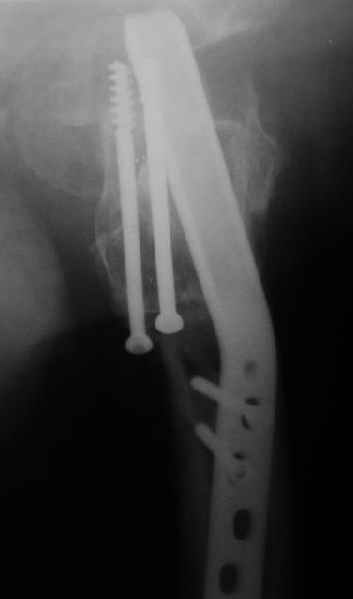

Мужчину 56 лет оперировали у нас в августе 2003 г. - вальгизируюшая остеотомия из-за позднего (через 2 мес. после травмы) поступления с переломом шейки бедра (картинки 1,2). Курильщик, соматической патологии не было. Сейчас поступил с жалобами на проблемы в области тазобедренного сустава, на снимках 3,4 видно вырезывание клинка.Чтоб можно посоветовать в этой ситуации? Заранее спасибо.

A male 56 years old was operated in Aug 2003 - valgus osteotomy performed because of delayed admission with neck fracture (2 months) images 1,2. Smoker, no other major medical problem. Now he re-admitted with the images 3,4.What would you do in the situation?THX in advance.

The osteotomy seems to be showing bony union. (New bone at the medial aspect). There is a big step in the union. The distal fragment is way out laterally.There is overiding of the neck over the head. The screws are out superiorly and the blade also coming out. There is no union of the neck fracture. The head does not seem to be normal- distorted in shape and probably starting of AVN too.

It will be a futile attempt now to get the neck fracture unite. The head has to come out and has to be replaced. Then comes the problem of the malaligned upper shaft. If it has united ( as what I think now) the union has to be undone and fragments aligned before introducing the stem.